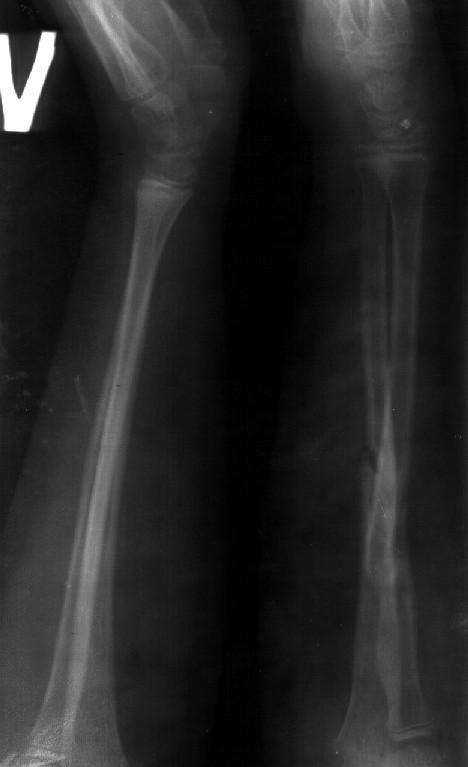

Re: Консолидированный перелом костей предплечья

Сделал симметричные снимки с максимальной супинацией и пронацией при согнутом предплечье в 90 град. Объем ротационных движений 90-100 град.